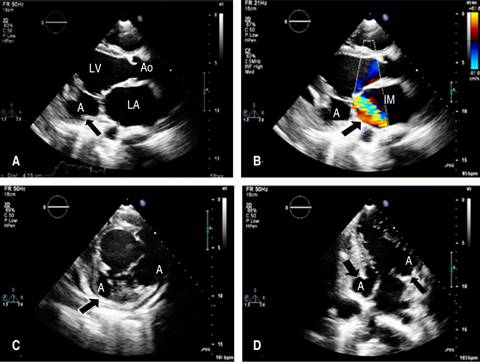

A 12-electrocardiogram was performed, showing sinus rythm but with signs of left chamber overload (Figure 1). A transthoracic echocardiogram was then requested, which revealed an image suggestive of aneurysm formation in mitral subvalvular projection located at the level of the posterior leaflet (in submitral projection) communicating freely with the LV and presence of severe MR with the enlarged left atrium (Figure 2). The transesophageal echocardiogram (TEE) confirmed a severe MR, and the single neck of the aneurysm connected to the LV is better visualized without a thrombus image within the aneurysm (Figure 2). Cardiac angiotomography (Figure 3A-C): illustrates mitral subvalvular aneurysmal dilatation and a communicating aneurysm (Figure 3D).

Figure 2: Transthoracic echocardiogram. A) Two-dimensional mode in long-axis parasternal view with the presence of an aneurysm in the basal portion of the LV posterolateral wall at the mitral subvalvular level (arrow). B) Colorful Doppler image with severe mitral regurgitation (arrow). C) Aneurysm (arrow). D) Fistulated aneurysm (arrow). A = aneurysm; LA = left atrium; Ao = aorta; LV = left ventricle; IM = insuficiency mitral.